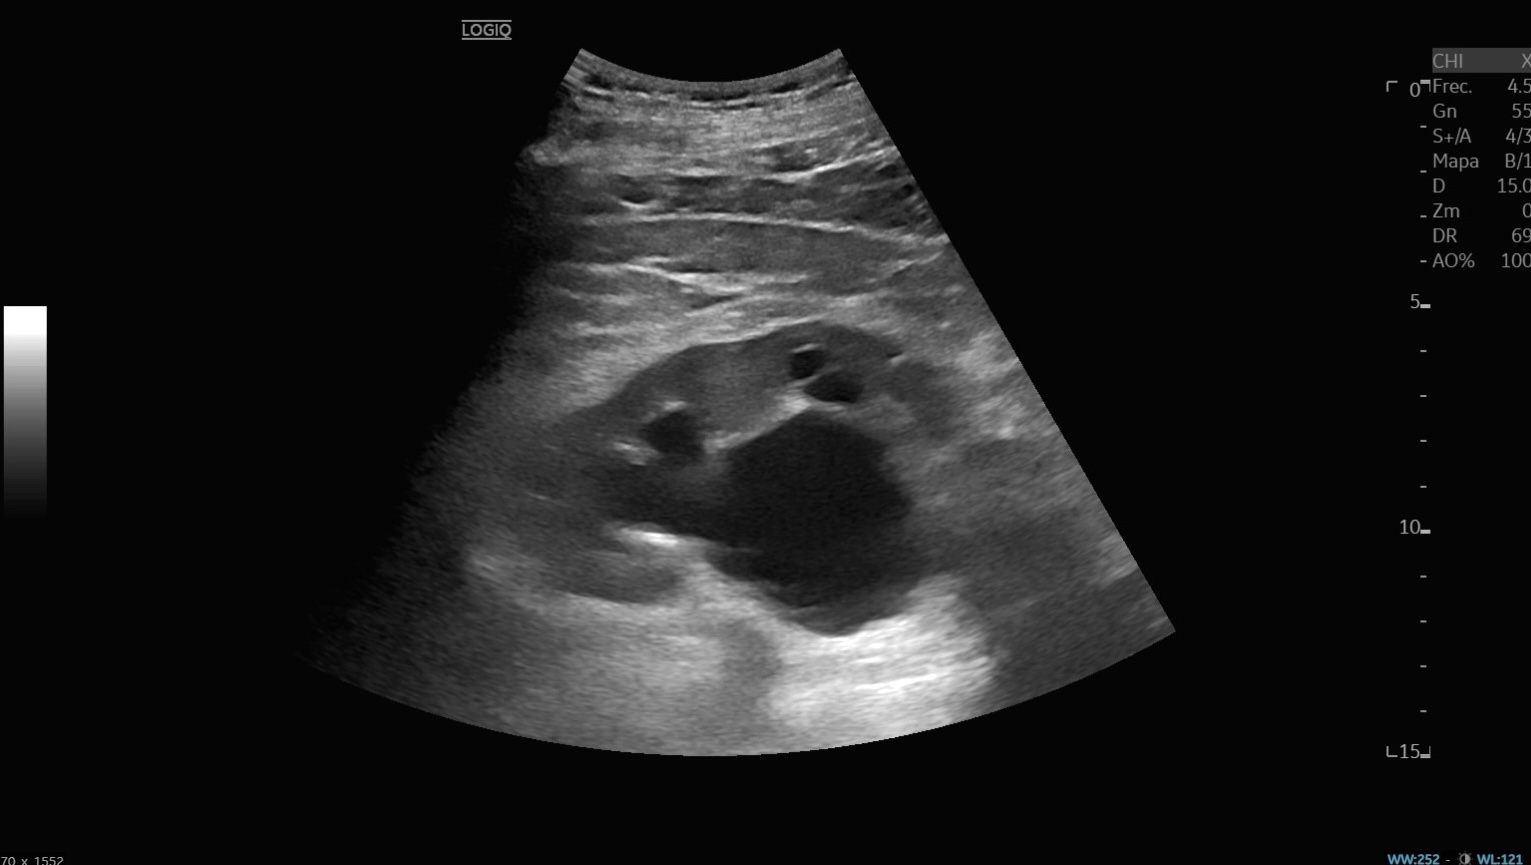

Ecografía abdominal: vejiga hiperdistendida con unos 3000 ml de orina y hidronefrosis bilateral moderada-severa, sin lesiones intravesicales ni causa obstructiva aparente. Analítica: anemia microcítica (Hb 9 g/dl), insuficiencia renal aguda grave (urea 409, creatinina 14,2), acidosis metabólica (pH 7,26; HCO₃ 6,3), PCR 19,7. Sedimento urinario positivo para infección.

Por el cuadro constitucional y vómitos, la primera sospecha fue neoplasia maligna. Sin embargo, la ecografía reveló retención urinaria masiva con afectación pielocalicial bilateral, orientando el diagnóstico hacia insuficiencia renal aguda obstructiva.